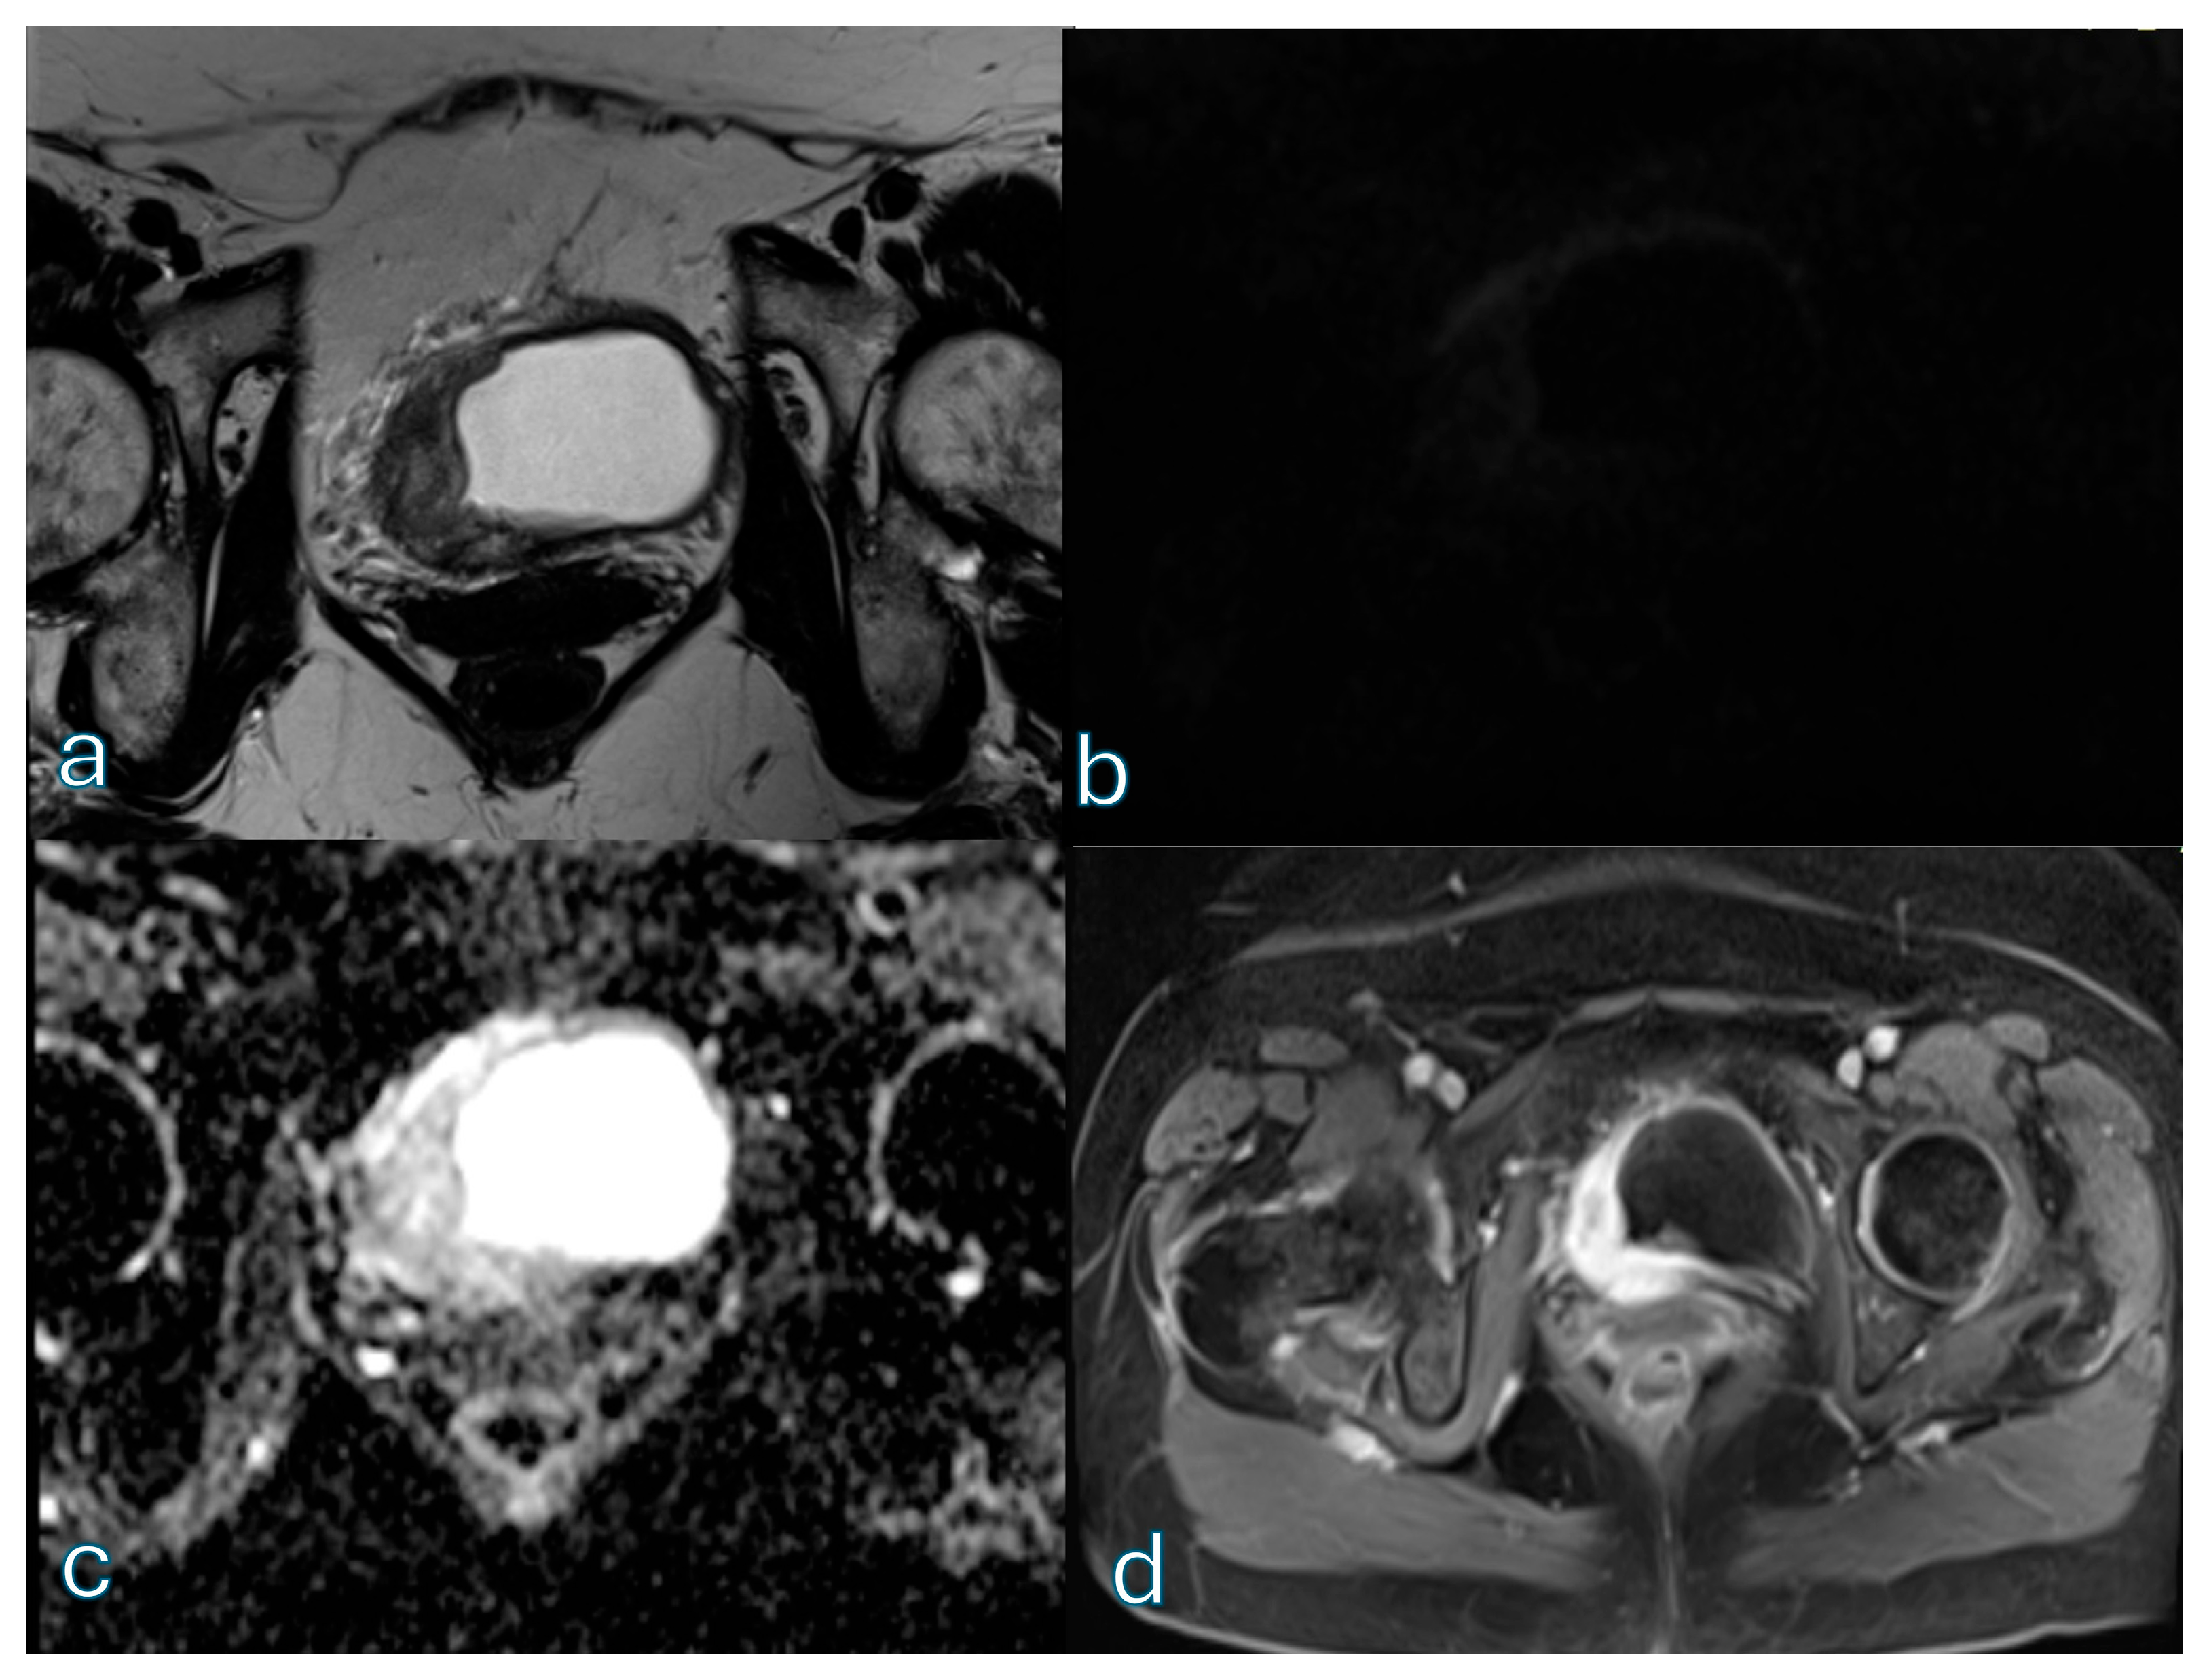

3.3. bpMRI Performance: Expert Reader